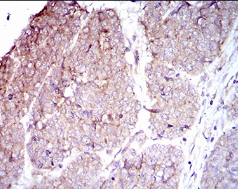

IHC    1/200 - 1/1000